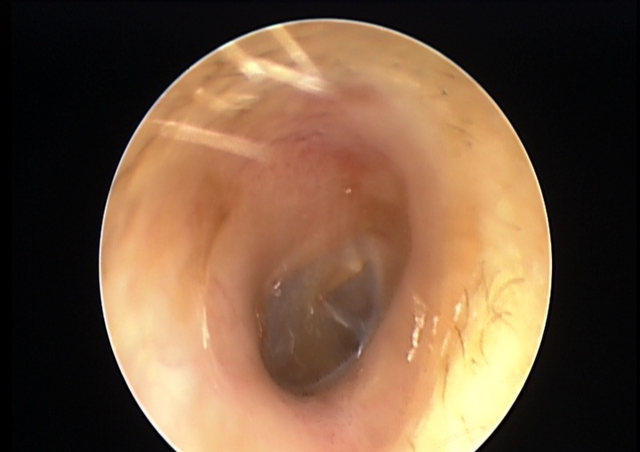

医生检查发现 , 他的双侧耳道表面布满密密麻麻的白色绒毛物体 , 被诊断为“外耳道真菌病” 。

▲治疗前

经过正规治疗后 , 小思的耳痒及耳闷症状逐渐好转 。

▲治疗后